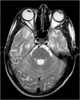

Subacute sclerosing panencephalitis

Subacute sclerosing panencephalitis (SSPE)—also known as Dawson disease—is a rare form of chronic progressive brain inflammation caused by slow infection with certain defective strains of hypermutated measles virus. The condition primarily affects children, teens, and young adults. [Source: Wikipedia ]